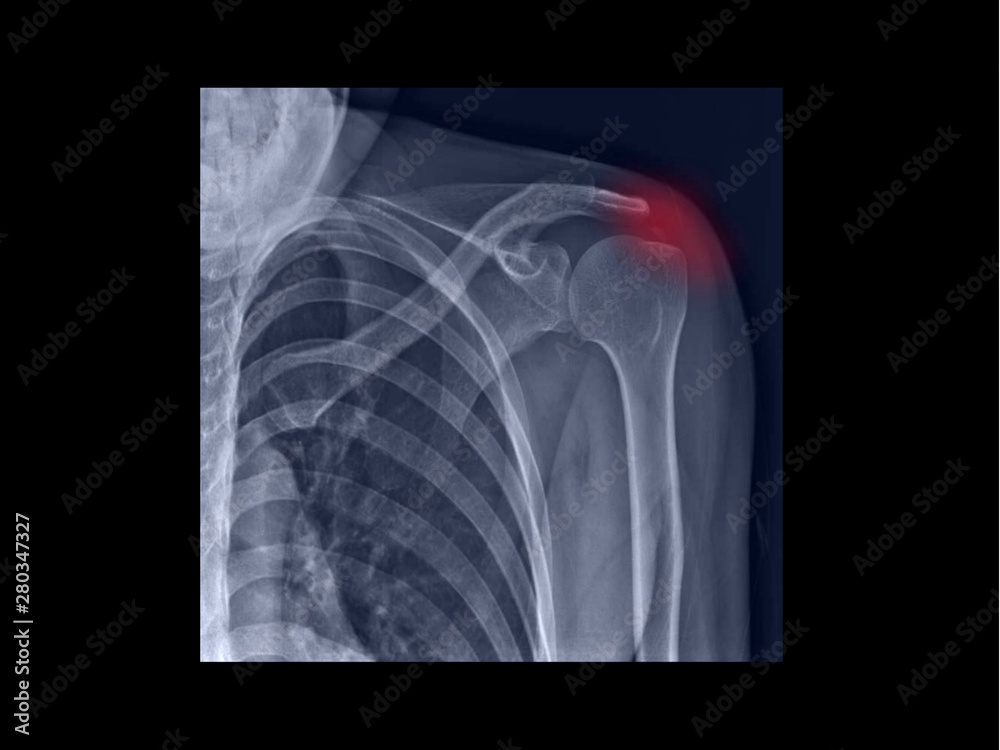

From stock.adobe.com

Fotka „Film Xray shoulder radiograph showing calcium deposit on What Do Calcium Deposits Look Like On X Ray This test measures the level of calcium in your blood. When your doctor tells you that you have calcified arteries, it is usually after you have had a coronary calcification scan. Microcalcifications are tiny calcium deposits that may be seen in thyroid nodules, some of which could be cancerous. Your healthcare provider may also order a calcium blood test. Calcifications. What Do Calcium Deposits Look Like On X Ray.